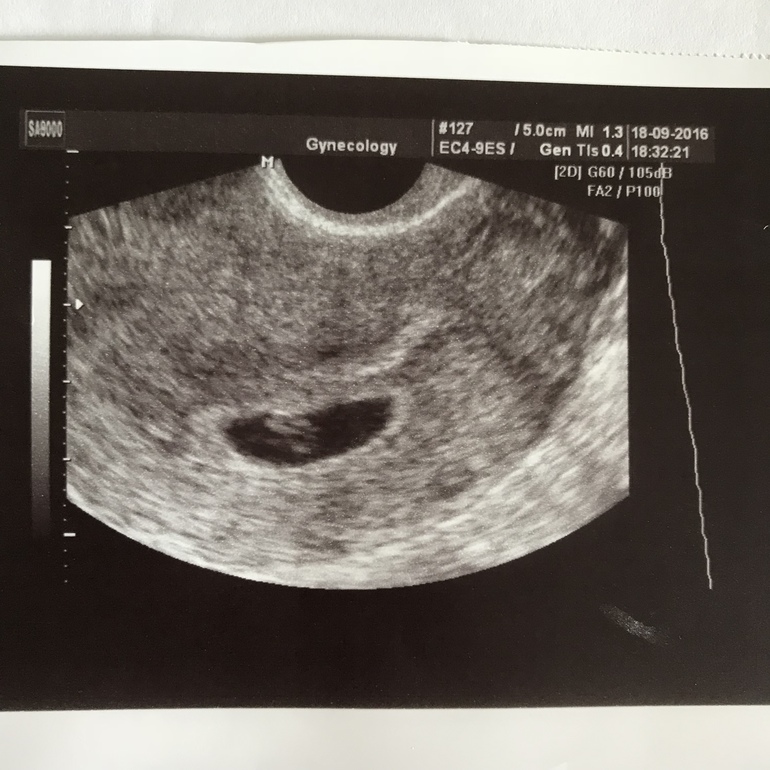

Первое фото это беременность 5 недель 2 дня

Второе фото это 5 недель и 2 дня при кисте

Видно невооруженным взглядом, что ничего похожего на беременность в матке нет на таком же сроке

И вот для сравнения УЗИ матки небеременной просто в середине цикла. Точно такая же как при кисте и 2х полосках тогда